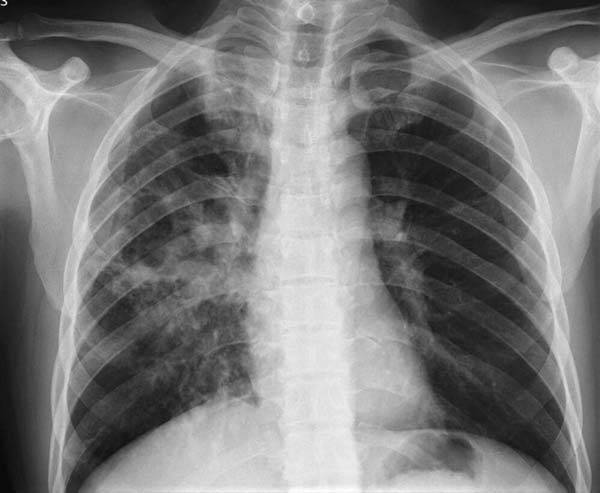

부동의 사망률 1위 ‘폐암’… 생존율은 2배로 올랐다

폐암의 국내 발생률이 최근 15년 간 꾸준히 올랐지만 생존율은 개선된 것으로 나타났다.

폐암 환자가 늘었지만, 생존율은 개선되는 추세다. 폐암 진단 후 환자의 1년 생존율은 2008년 48.6%에서 2023년 68.4%로 올랐다. 5년 생존율은 18.5%에서 35.7%로 상승했다.

한편, 생존율이 조금 증가해도 여전히 사망률이 가장 높은 암은 폐암이다. 국내 기준 폐암은 5년 생존율이 40.6%에 불과하다. 2023년 암으로 사망한 8만5천271명 중 21.9%에 달하는 1만8646명이 폐암을 앓았다. 이는 간암(11.9%), 대장암(11.0%), 췌장암(9.0), 위암(8.5%)과 비교해 2배 이상 높은 수치다.

폐암 사망률이 높은 이유는 뚜렷한 초기 증상이 없기 때문이다. 실제 폐암 환자의 15% 정도는 무증상일 때 폐암으로 진단되고, 진단받았을 때는 이미 암이 어느 정도 진행된 경우가 많다. 폐암의 평균 발병 연령이 70.2세의 고령이라는 점도 사망률이 높은 원인이다. 낮아진 면역력에 각종 합병증이나 심장·뇌혈관 질환 등이 동반될 수 있기 때문이다.